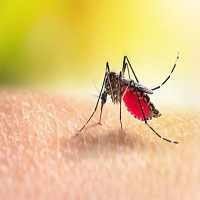

ডেঙ্গু: ২৪ ঘণ্টায় মৃত্যু ২, আক্রান্ত ৩২৬ গত ২৪...